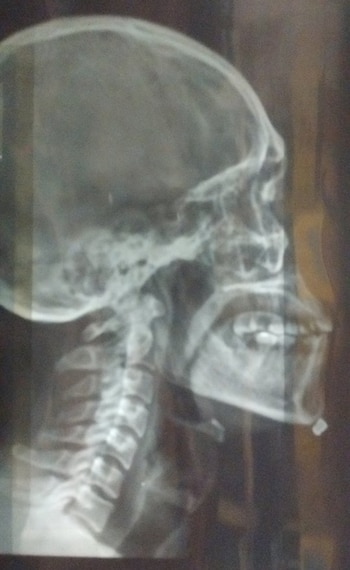

Uno de los miembros del grupo recibió tres disparos en el cuerpo. El más peligroso le impactó en el mentón. "No es un arma de juguete. Era un rifle que tiraba a repetición y creemos que debe tener muy buen alcance, porque estamos alejados de la calle y dispararon con mucha precisión", agregó Juan Pablo, quien aseguró que "nuestro guía también sufrió un disparo debajo de la axila".